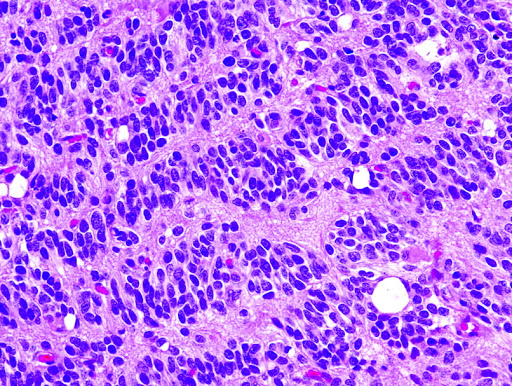

Segmented the tiny nuclei in the histopathological images by using a sophisticated voting algorithm to find markers and then applying the Marked Watershed algorithm on top of them using MATLAB.